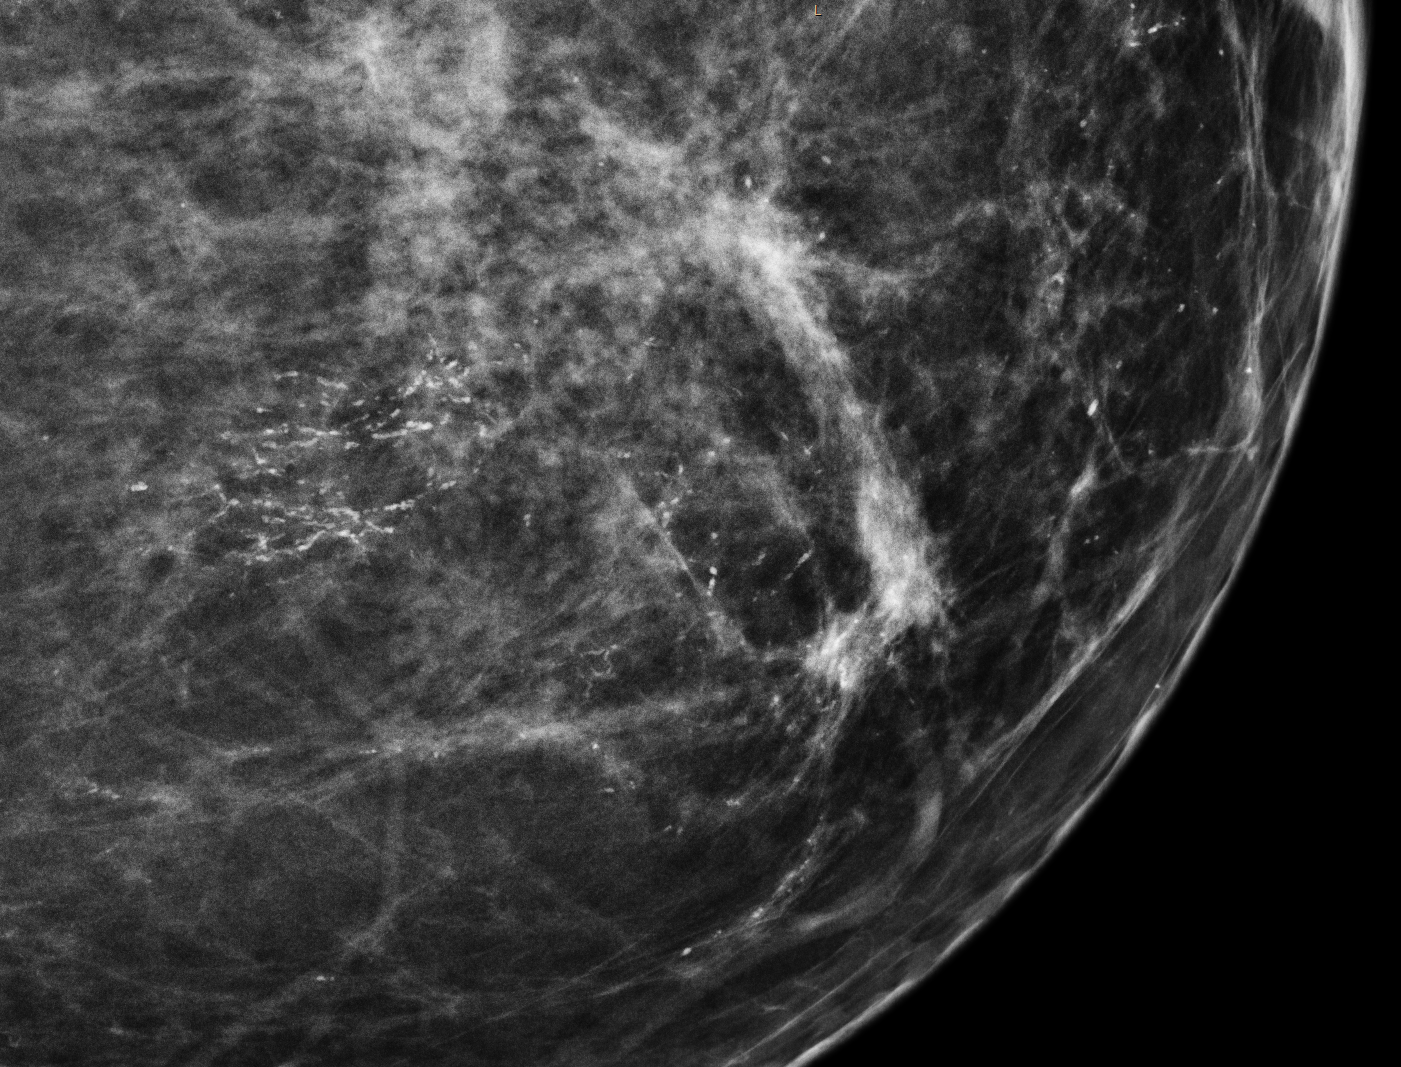

Dense breast tissue also makes it difficult to detect cancer using traditional mammography alone. On a mammogram, dense breast tissue appears white – but so do breast masses and cancers. In contrast, cancers are easier to detect in non-dense breasts because fatty tissue appears black on a mammogram, so the white cancer stands out like a light bulb against a black background.